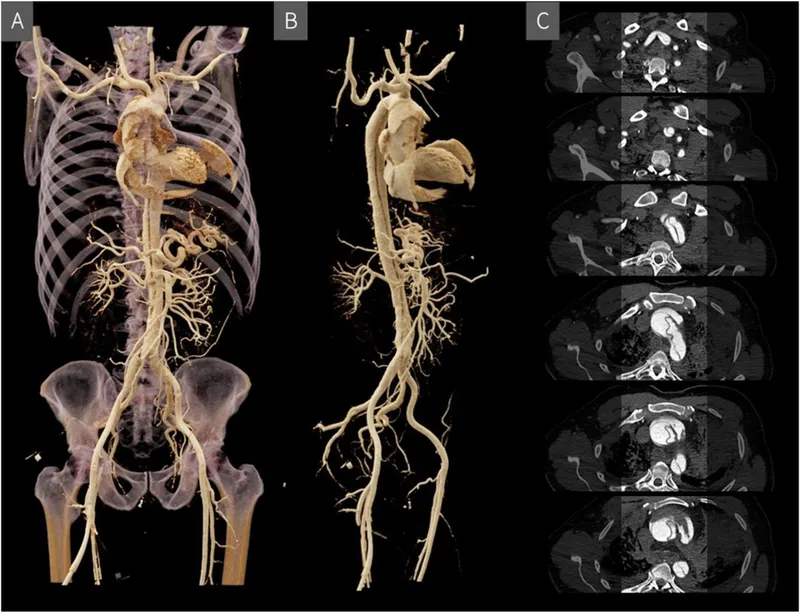

- Virtual Autopsy (Virtopsy - Techy Tools):

- PMCT & PMMRI.

- Pros: Non-invasive, excellent documentation (3D), detects gas embolism, occult fractures, foreign bodies.

- Cons: Cost, expertise, poor soft tissue detail (PMCT), limited toxicology.